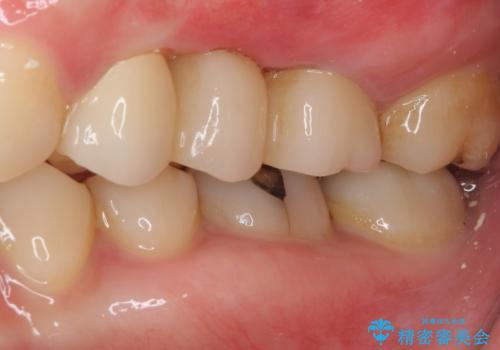

抜歯をしたことで、ずっと気になっていた異臭から解放されました。

手前の歯を削ってブリッジ治療とするのか、インプラントによる治療とするのか、悩んでいらっしゃいましたが、奥歯の銀歯もセラミックにしたいとのことで、ブリッジ治療を選択されました。